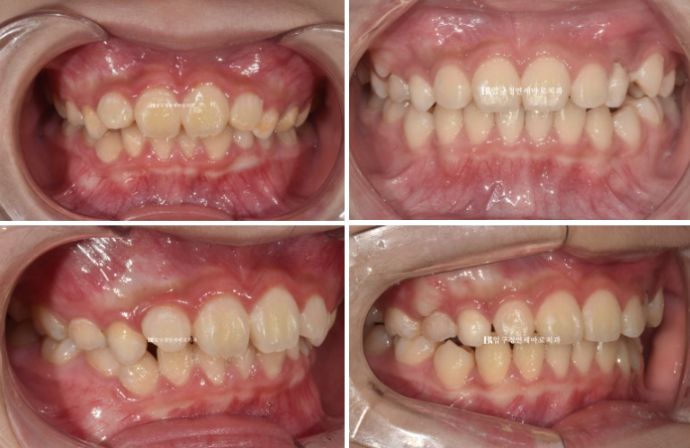

마지막 장치를 낀 후 모습입니다.

24.07

덧니처럼 나와있던 송곳니는 잘 배열이 되었고 그 사이 마지막 유치 어금니 4개가 빠지고 영구치 작은 어금니가 내려오는 중입니다.

드디어 영구치열에 접어들었습니다.

작은어금니가 잘 내려와서 교합이 될 수 있도록 금속 고리를 치아에 붙이고 뺏다 꼈다 하는 고무줄 처방도 들어갔습니다.

그렇게 두달 간 고무줄을 끼면서 작은 어금니 교합을 안정화 시켜 24년 9월 드디어 모든 치료가 마무리 되었습니다.

24.09

중심선은 정확히 맞고

어금니 교합은 1급 교합관계를 보입니다.

배열도 좋습니다.

그 사이 마지막으로 맹출하는 두번째 큰어금니까지 잘 나오고 있습니다.